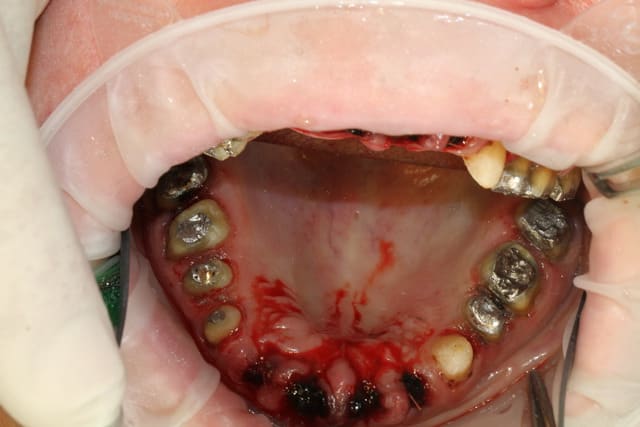

extract récente implant + Vitalos

essai de photos

votre avis?

Vous etes vraiment indulgents entre copains :

mis à part les couleurs incroyables et l'exposition mauvaise, le cadrage est nul : il faut penser à ce que l'on veut montrer en faisant la photo, et se mettre à la place de l'observateur. Ici, c'est complètement fouillis et pas du tout pédagogique. Les miroirs sont extremement mal placés.

Salut Xavier, je trouve la première série de photo correcte au niveau exposition et rendu, par contre comme l'a dit Marc pour le cadrage ce n'est pas du tout ça.

Sur tes photos, on ne sait pas trop ce que tu as voulu montrer, la première chose qu'on voit, c'est un miroir !

Je suis loin d'être un expert, mais amha, il faut que tu t'achètes de vrais miroirs photos (pseudo-carré ou pseudo-rectangulaire) et que tu fasses un choix: soit tu photographie en indirect par l'intermédiaire du miroir (et on ne doit pas voir les limites de ton miroir, le recadrage étant bien entendu possible à postériori), soit tu photographies en direct, et donc le miroir ne sert à rien. Sur tes photos, tu as essayé de faire les deux à la fois et au final on ne voit rien.